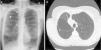

During the following 3 months, no significant clinical or functional improvement was observed. The imaging studies revealed an unresolved interlobar air cavity and persistent RUL atelectasis (Fig. 1). It was suspected that this voluminous cavity counterbalanced the benefit of volume reduction obtained by RUL atelectasis, and thus, the remaining valves were removed. The apical valve was inaccessible due to bronchial angulation; however, the posterior one was removed successfully.

Despite removal of the second valve, RUL atelectasis and interlobar air cavity persisted. A chest tube was then placed inside the air cavity under CT guidance, and revealed a perpetual air-leak, explaining the long-lasting pneumothorax (for more than 3 months, after the initial procedure). The patient was referred for thoracic surgery to restrain the pneumothorax and to achieve lung reduction. Due to lobar atelectasis, a right upper lobectomy was chosen instead of a classical LVR surgery. This procedure halted the air leak, permitting removal of the chest drain after 3 days. At clinical follow-up, several months after the surgical LVR, no significant clinical or functional improvement was observed and the patient was referred for lung transplantation evaluation.